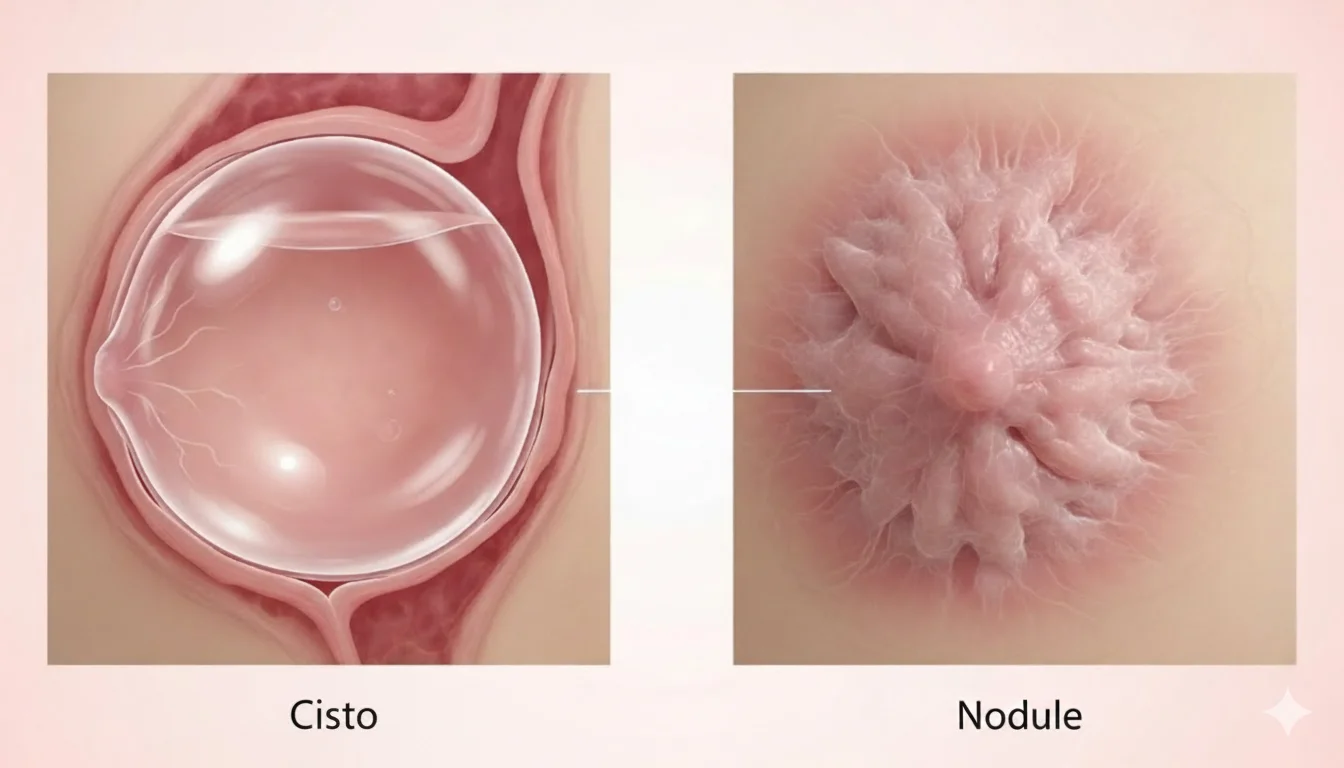

Cistos e Nódulos Mamários: Entenda as Diferenças Cisto de mamaÉ uma bolsinha cheia de líquido, muito comum principalmente a partir...

Tipos de “caroços” na mama: o que podem significar? Descobrir um “caroço” na mama é motivo de preocupação para muitas...